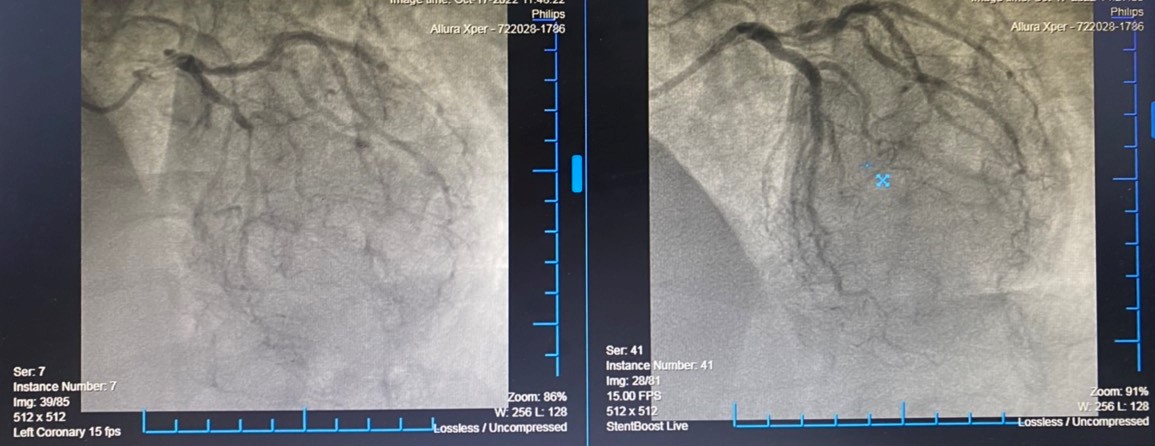

Kết quả chụp mạch vành của bệnh nhân phát hiện tổn thương rất nặng toàn bộ hệ động mạch vành: Hẹp khít lỗ vào thân chung động mạch vành bên trái, hẹp khít đoạn 2 động mạch liên thất trước, tắc hoàn toàn mạn tính Stent cũ động mạch vành bên phải, có tuần hoàn bang hệ một phần từ bên trái sang.

Sau khi đã hội chẩn và thống nhất các phương án điều trị, xác định thủ phạm chính gây nhồi máu cơ tim cấp lần này là Động mạch vành bên trái vị trí thân chung và hẹp khít LAD2, bệnh nhân được can thiệp đặt 2 Stent LM-LAD2. Ekip can thiệp đã rất thận trọng, tiến hành mở thông hoàn toàn thân chung động mạch vành trái, đặt 2 stent thành công. Quá trình can thiệp thuận lợi, sau can thiệp, bệnh nhân đã hết đau ngực, khó thở và hồi phục tốt.